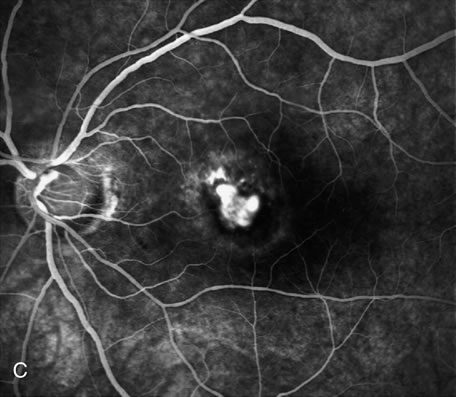

Furthermore, FA helps in recognizing two types of CNV: classic and occult. Classic CNV consists of a well-defined neovascular membrane, which is apparent in the early phase of the angiogram and shows late leakage of dye beyond its boundaries (Fig. 7 and 8). Occult CNV is seen on by FA as an area of late hyperfluorescence of undefined origin or as a neovascularized PED (Fig. 9 and 10 ). Mixed-type CNV is predominately classic or minimally classic depending on whether the classic component is more or less than 50% of the entire lesion (Fig. 11).

Fig. 7. Composite photograph of fluorescein angiography study in a patient with classic, subfoveal choroidal neovascularization (CNV) in the right eye. A The classic neovascular membrane appears as a well-defined area of hyperfluorescence in the early phases of the angiogram. There is leakage of dye from the classic net in the subretinal space throughout the study. B. In the late phase of the study, the edges of the CNV are fuzzy and indistinguishable.

Fig. 8. A. Color photograph of subfoveal classic choroidal neovascularization (CNV). The neovascular membrane appears as a dirty gray, subfoveal lesion surrounded by exudative neurosensory detachment. B–D. Fluorescein angiography demonstrates early hyperfluorescence and late leakage of the CNV.